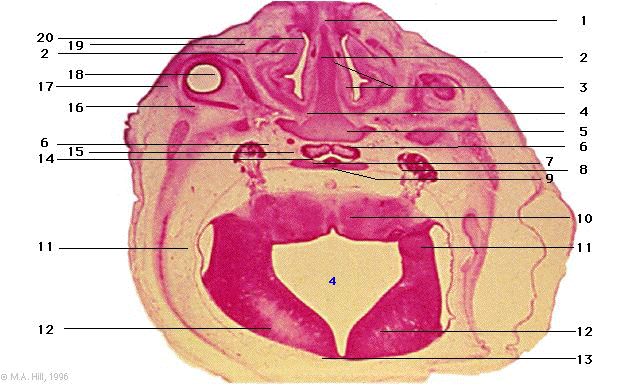

1 |

nasal plug (transient) |

2 |

vomeronasal organs |

3 |

nasal conchae |

4 |

perpendicular plate of ethmoid cartilage |

5 |

lesser wing of sphenoid |

6 |

internal carotid arteries |

7 |

neurohypophysis |

8 |

trigeminal ganglion (V) |

9 |

sphenoid bone |

10 |

brainstem (pons) |

11 |

lateral recess of 4th ventricle |

12 |

cerebellum (intraventricular) |

13 |

roof of ventricle |

14 |

remnant of Rathke's pouch |

15 |

adenohypophysis |

16 |

lateral rectus muscle |

17 |

retinal pigmented epithelium |

18 |

medial rectus muscle |

19 |

nasolacrimal duct |

20 |

nasal septum |